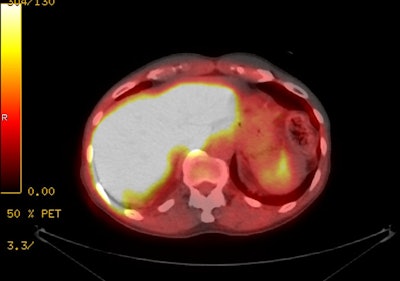

|

18F-Fluciclovine with

normal intense tracer activity in the liver, pancreas,

and urinary bladder. |